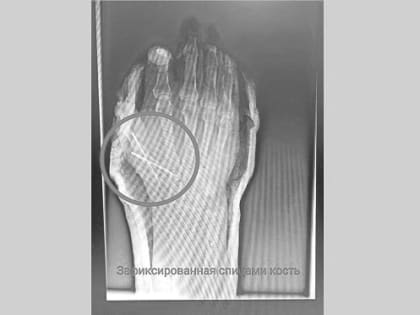

В Татарстане врачи спасли от ампутации палец 54-летнего мужчины, отрезанный болгаркой

Врачи Нижнекамской центральной районной многопрофильной больницы рассказали о спасении 54-летнего пациента, который работая на даче случайно травмировался болгаркой.

Опасный инструмент: врачи спасли дачнику палец, отрезанный болгаркой

В Татарстане врачи спасли мужчине палец на руке – был риск его полной ампутации.